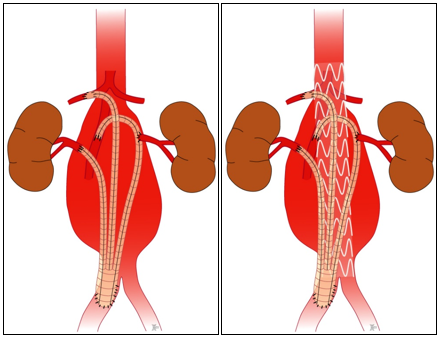

Die erste offene chirurgische Aortenaneurysmaoperation, wie sie auch heute mit kleinen Veränderungen durchgeführt wird, wurde 1951 von dem Franzosen Charles Dubost erstmals eingeführt. Nach Eröffnung der Bauchhöhle, wird hierbei der aneurysmabetroffene Anteil der Hauptschlagader aufgeschnitten und eine Kunststoffprothese (Polyester/Dacron) in die gesunde Aorta eingenäht.

Im Jahre 1991 wurde von J.C. Parodi und N. Volodos ein neues Verfahren zur endovaskulären Ausschaltung von Aortenaneurysmen vorgestellt. Hierbei wird ein Stentgraft (mit Stoff ummanteltes Drahtgerüst) über die Leistenarterie operativ eingeführt, unterhalb der Nierenarterien platziert und freigesetzt. Das Blut fließt dann nicht mehr im Aneurysma sondern in dem Stentgraft und das Risiko der Ruptur ist damit ausgeschaltet. Voraussetzungen für die Anwendung dieses Verfahrens sind:

Bei komplexen Befunden müssen hin und wieder maßgefertigte Stentgraftprothesen, teilweise mit Fenestrierungen (Aussparungen) oder Seitenarmen für Eingeweide-arterien ausgemessen und bestellt werden. Die Produktion dieser Prothesen kann bis zu 10 Wochen Zeit in Anspruch nehmen.